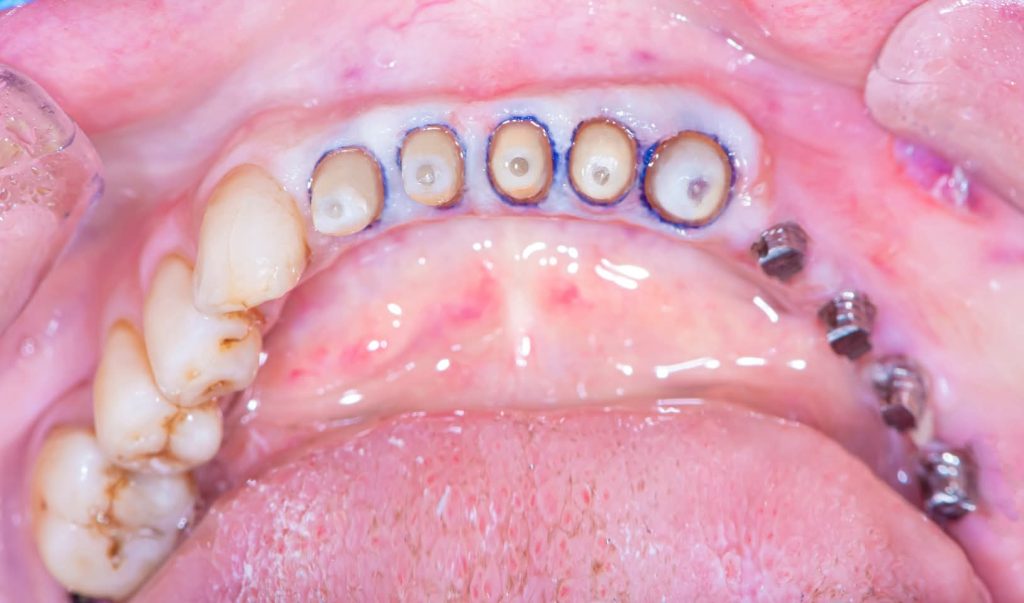

2. Corrective Phase:

This phase included all necessary corrective procedures:

Extraction of hopeless teeth.

Endodontic treatments.

Replacement of old, defective fillings.

Tooth build-ups to the new vertical dimension of occlusion, aided by the silicone indices.

Removable prostheses were inserted, and the patient was monitored for one month.

Minor occlusal adjustments were made during this period to achieve a more stable, comfortable occlusion and proper phonetics.

3. Definitive Phase:

This phase began with the upper arch:

Placement of implants in the free-end areas.

Preparation of teeth and insertion of the fixed prosthesis.